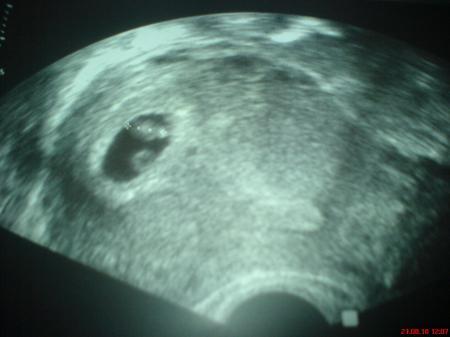

und hier nochmal das aller erste us bild

Auf dem ersten Bild hätte ich gesagt: Zwillinge. Auf den Bildern aus der 13. SSW seh ich nur eins und auf dem letzten kann es sein, dass es ne Spiegelung ist? Sonst müssten die ja genau parallel sitzen. Also ganz ausschließen würde ich Zwillis nicht, halte das aber für sehr, sehr unwahrscheinlich, da dein Arzt das bestimmt erkannt hätte, denn soweit ich sehe, hat er ja gute Geräte. Berichte bitte am Dienstag, ich bin gespannt!

also ich hab das Bild aus der 22. Woche mal extrem vergrößert. Ich sehe da 2 Gesichter. Beim hinteren sieht es zwar bissl wie ein Schatten aus, aber dieser hat ein Ohr! Also... hmm... ich würde am Montag nochmal zum Arzt und auf nen weiteren US bestehen, der soll das eindeutig ausschließen, wenn er der Meinung ist, es sei nur eins! oder gleich nen anderen Arzt aufsuchen. Aber wenns tatsächlich zwei sind, sind die eineiige :D Hoffe du hast noch keinen KiWa, sonst brauchst du nen neuen und größeren *lol*

Kann es sein dass auf dem ersten Bild einfach noch der Dottersack zu sehen ist??? Und beim letzten Bild sieht es ein bisschen wie ein 2. Köpfchen aus, aber die Bilder sind so gut, ich glaub ja nicht dass dein FA da wirklich ein Kind übersehen könnte... LG

Habe jetzt lange mit meinem Schatz spekulirt, beim ersten bild sehen wir beide 2, bei mir war da nur ein punkt... beim 2 Bild glauben wir nur eins zu sehen, aber die können ja auch nebeneinander liegen und dann sieht man ja nur das vordere... Beim 3. Bild also das 3 D bild sehen wir devinitiv zwei köpfchen 2 linke ohren und 4 Beinchen... Es hats ja schon gegeben das frau ein kind erwartet hat und zwei rausgekommen sind. Ich wage es zwar zu bezweifeln bei der heutigen technik, aber die kleinen können sich auch gut verstecken, besonders wenn ein Geschwisterchen einem "dekung" bietet. Berrichte auf jeden Fall wenn du am Dienstag wieder da bist bin nun auch neugierig...

zwillinge aus das hat auch kopf und öhrchen. lg dklein23